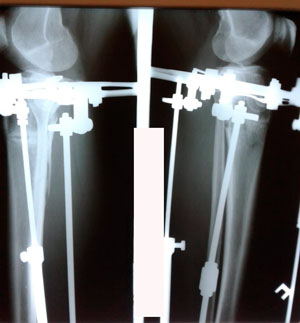

Исходник - 44 года.

Дата операции - 17.03.2020

Дата снятия аппаратов - 17.06.2020

Срок сращения - 90 дней.